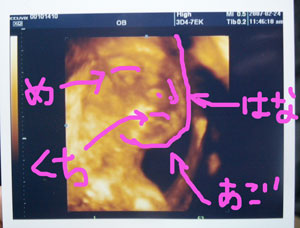

また縁取りしたよププ━(艸ε≦●)━ッッ♪

270.jpg

下から撮ったかんぢですハート

わかるかなー???

口おっきく開けて羊水飲んでるところもバッチリ

確認☆☆